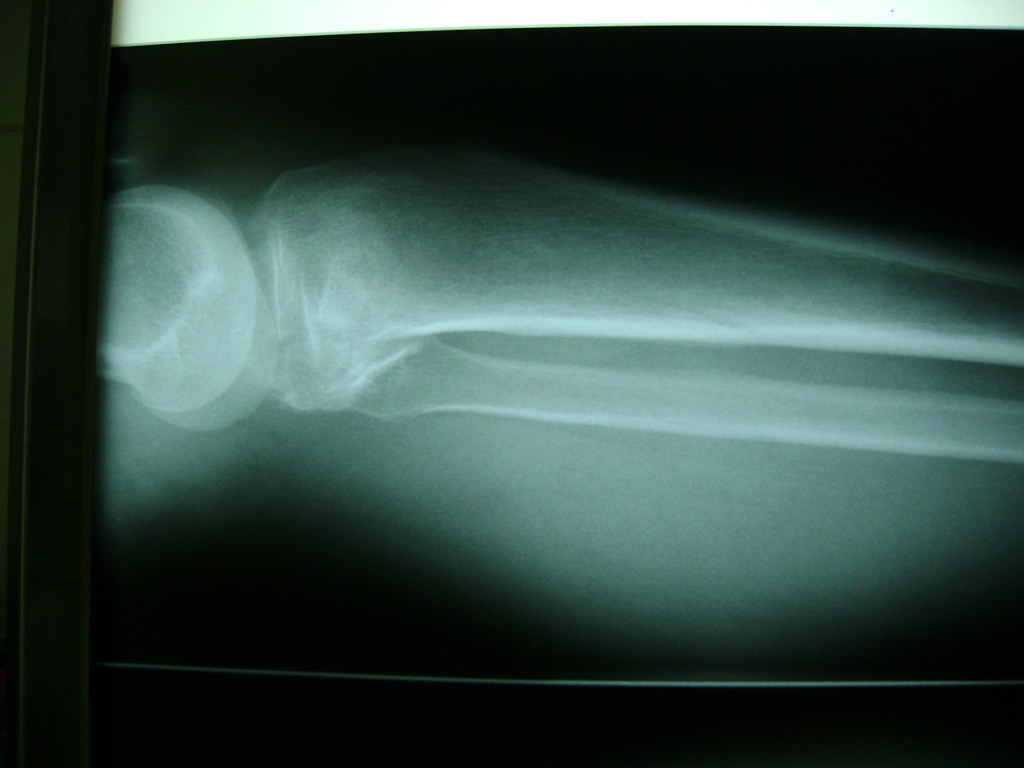

Cirugía de Fémur - Rodilla

La artroscopia de rodilla es un cirugía en el cual la estructura interna de la articulación es examinada ya sea para realizar un diagnostico o para realizar un tratamiento, este procedimiento se realiza utilizando un instrumento parecido a un pequeño tubo llamado artroscopio.